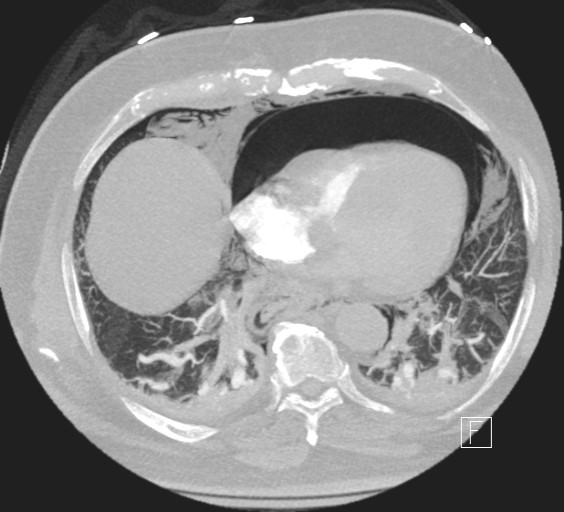

A 72-year-old gentleman with achalasia who weighed 91 kg was admitted for an elective POEM procedure (Figure 1). The procedure started with stable hemodynamics on a constant ventilator setting of respiratory rate of 10-16/hr; tidal volume of 443; positive end-expiratory pressure (PEEP) of 5 cm H2O; positive inspiratory pressure of 22-24; end tidal carbon dioxide of 28; arterial oxygen saturation of 100. However, 45 minutes into the procedure, the patient went into pulseless electrical arrest. The scope was withdrawn, and he was revived after 10 minutes of cardiopulmonary resuscitation. The procedure was aborted and he was transferred to the ICU intubated, critically ill, and on escalating doses of epinephrine and norepinephrine. Follow-up diagnostic imaging (Figures 2 and 3) showed a small heart with air tracking around it, the mediastinum, the esophagus, and the aorta, confirming tension pneumomediastinum.

Under echo-guided pericardiocentesis, the cardiogenic shock was instantaneously reversed upon entry of the needle into the highly pressurized pericardial sac. A total of 600 cc of air and very minimal serosanguinous fluid was evacuated through a 3-way stopcock with a 50 cc syringe. The patient's inotropic support and pericardial drain were discontinued within 36 hrs. Under endoscopic guidance, botox injections were performed 4 days after his cardiac arrest. He was ultimately extubated on postoperative day 8, after being treated for aspiration pneumonia. Follow up esophagram done a month later showed findings compatible with achalasia with no evidence of a leak. The patient was discharged after 54 days due to complications of aspiration pneumonia, sepsis, and acute kidney injury. During a 6-month follow-up visit, the patient's esophagogram showed achalasia, but he reported relief of symptoms of achalasia.